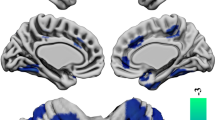

Associations between CG and illness insight

In SPM-based multiple regression analyses for OSSTI-A, significant negative association were found in the left inferior parietal lobule (IPL) and the right superior parietal gyrus, and significant positive associations were found in the right superior frontal and the precentral gyrus (M1). For OSSTI-I, significant negative associations were found in the left superior frontal gyrus and significant positive associations in the right supramarginal gyrus (see also Fig. 1 and Table 2).

Negative and positive associations for CG and OSSTI-I and OSSTI-A. Results derived from whole-brain regression analyses implemented in SPM12, adjusted for age, gender, OLZe, PANSS (p < 0.005, uncorrected, expected voxels per cluster). CG cortical gyrification, OLZe Olanzapine equivalents, OSSTI Osnabrueck Scale of Therapeutic Attitudes and Identification of Psychological Problems in Schizophrenia (OSSTI-A adherence), OSSTI-I identification of disease-related symptoms), PANSS Positive and Negative Syndrome Scale